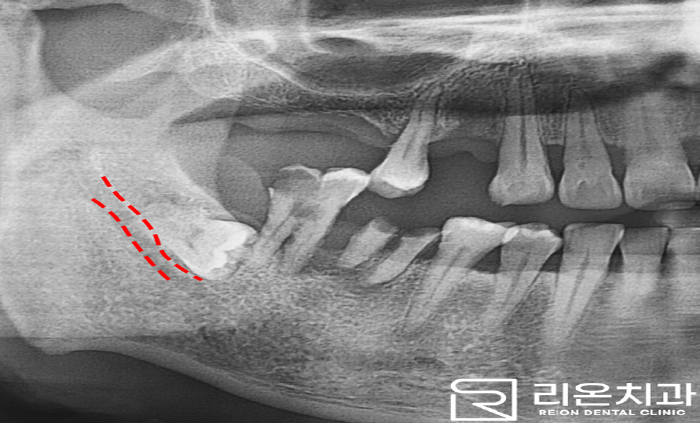

하악(아래턱)은 46, 47번 ext 후 진행하는데요,

이때 옆에 누워있는 치아가 보입니다.

촬영일: 2023.01.03

우리가 흔히 알고 있는 사랑니이며 그 아래 중요한 구조물인 하치조 신경관(mandibular canal)이 있기에 이를 고려하여 시술하게 됩니다.